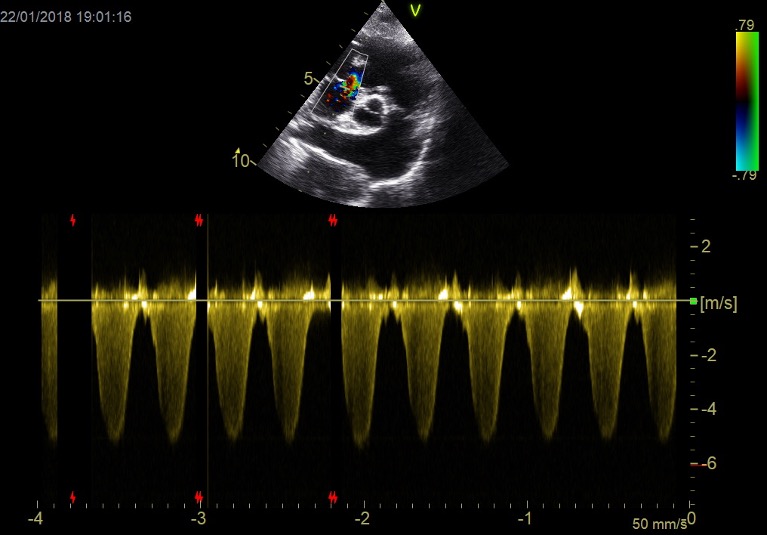

Flujo transmitral (Doppler pulsado): relación E/A, tiempo de desaceleración.

Haz clic en la imagen para obtener una vista más ampliada

Doppler tisular (TDI): onda e’ (relajación) y E/e’ (estimación de presiones de llenado).

Aurícula izquierda (LA/Ao): refleja cronicidad de la sobrecarga.

Flujo venoso pulmonar (si es posible).

En la disfunción diastólica, el problema está en el llenado ventricular alterado debid

o a rigidez y/o alteraciones estructurales. Y su principal signo clínico es la congestión a nivel pulmonar (si el problema es izquierdo) o abdominal (ascitis) si es del lado derecho.

Pregunta 2

En un paciente con enfermedad valvular degenerativa mitral, en estadio C con diagnóstico previo de edema pulmonar, tras el tratamiento con furosemida, su perfil de flujo transmitral previo mostraba una pseudonormalización, con una velocidad pico E de 1,1 m/s. En la revisión, este es ahora su perfil de flujo transmitral. ¿Qué está pasando? ¿Qué más podemos hacer por el paciente?

Existe una progresión de la patología hacia una disfunción diastólica restrictiva, con un aumento de la velocidad pico E hasta 1,76 m/s, lo que indica que el paciente es refractario al tratamiento. Posiblemente continúe con frecuencias respiratorias elevadas. Habría que reevaluar si existe resistencia a los diuréticos y trabajar en reducir la poscarga (presión arterial). Además, según la edad del paciente, podría ser candidato a cirugía mitral edge-to-edge (si cumple criterios anatómicos y funcionales) y, en caso de no ser idóneo, podría considerarse la septostomía auricular.